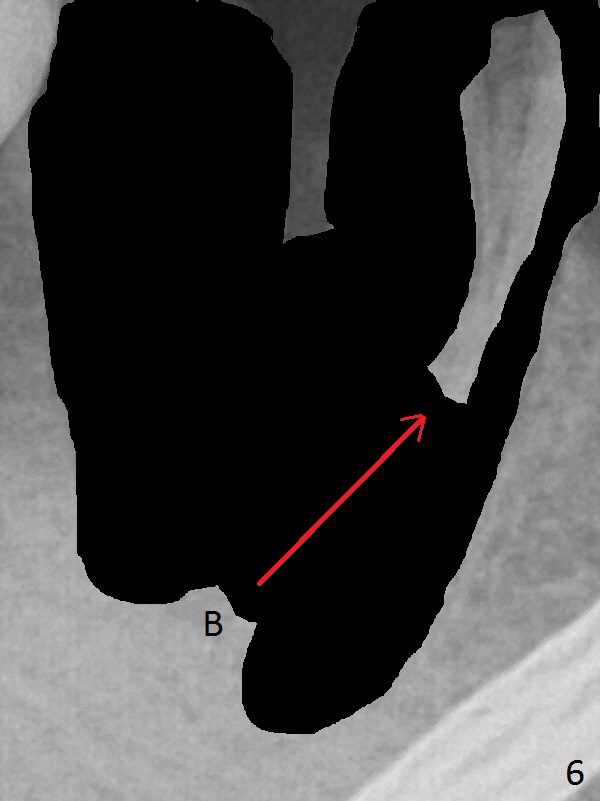

A 43-year-old man has residual roots at #30 (Fig.1). The mesial (M) and distal (D) roots approximates each other so close that the septum is thin (Fig.1,3-5). The latter is unfavorable for osteotomy. After extraction (Fig.5), the middle of the septum (Fig.8a (axial section of the sockets)) will be sectioned (Fig.6, 8b,c) prior to initial osteotomy (Fig.7,8d). The depth of the latter will be ~ 5 mm (Fig.2 red line) for a 13 mm (pink line) IBS implant.